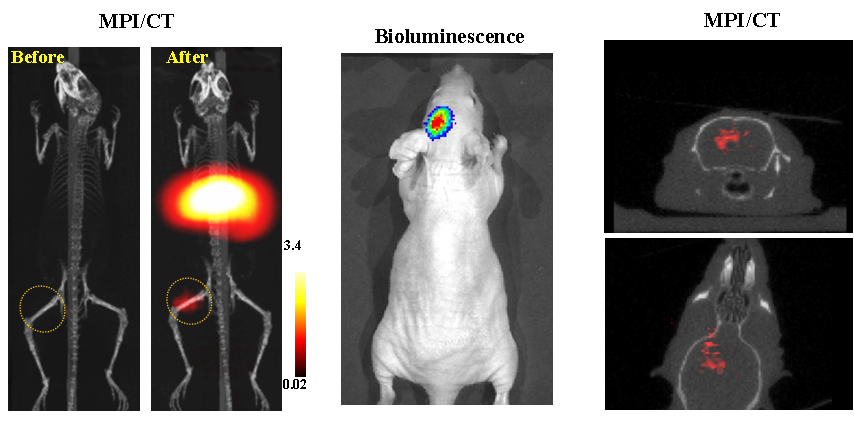

今年二月份,宋国胜教授与斯坦福大学饶江宏教授合作,通过系统的研究获得了影响磁性粒子成像信号的作用规律和关键原理,开发了新型磁性粒子探针---FeCo合金粒子,并首次应用于磁性粒子成像(MPI)。该造影剂在极低含量时(5 ng)仍具有很强的造影效果。这意味着,未来在进行人体成像时,可以使用更小剂量的造影剂,从而避免高剂量造影剂引起的肾肝损伤。基于MPI的直接成像原理,我们可以对造影剂进行正相和无背景干扰的活体成像,极大地提高信噪比。这项技术为肿瘤早期诊断、癌细胞示踪、脑中风、药物输送治疗、肺部灌注成像、胃肠出血、神经退行性疾病、磁热治疗等在活体中的可视化研究,提供了强有力的手段。相关研究成果以色情导航

为第一单位发表在Nature 子刊《Nature Biomedical Engineering》。该期刊是“生物医学工程”的顶级期刊。宋国胜教授为该论文的共同通讯作者。